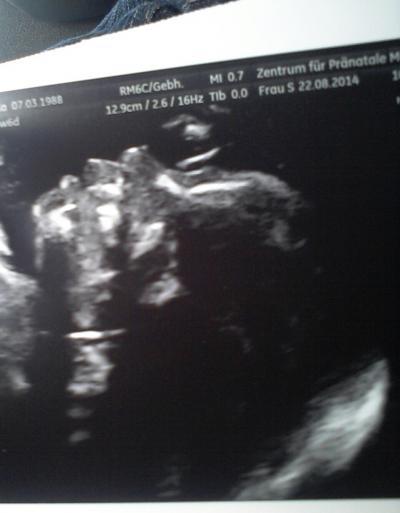

... hallo ihr lieben, soeben sind wir von der feindiagnostik wieder heim gekommen... es wurde nun nochmal bestätigt, das wir ein mädchen erwarten... :) :) :)... ... sie ist zeitgerecht entwickelt und gesund... laut arzt gibt es rein garnichts zu bemängeln... wir sind darüber sehr froh... ... was mir allerdings in dem auswertungsbogen aufgefallen ist, ist das der KU/ AU über dem durchschnitt liegt (1,312)...genauso wie die dopplermanternale gefäße: links; PI 1,21; RI 0,64 und rechts; PI 1,05; RI 0,60... hat jemand von euch damit erfahrungen? ... liebe grüsse und kommt gut in das wochenende... :) :) :)...

was für ein tolles Bild! Glückwunsch zur kleinen Maus! hört sich doch alles gut an! Allerdings kann ich zu dem wegen nichts sagen!

leider so gar keine Ahnung, aber ein sehr schönes Bild hast du da!

mache Dir keine Sorgen die Ärztin hätte schon was gesagt wenn was nicht i.O. wäre , super schönes Bild LG Bella